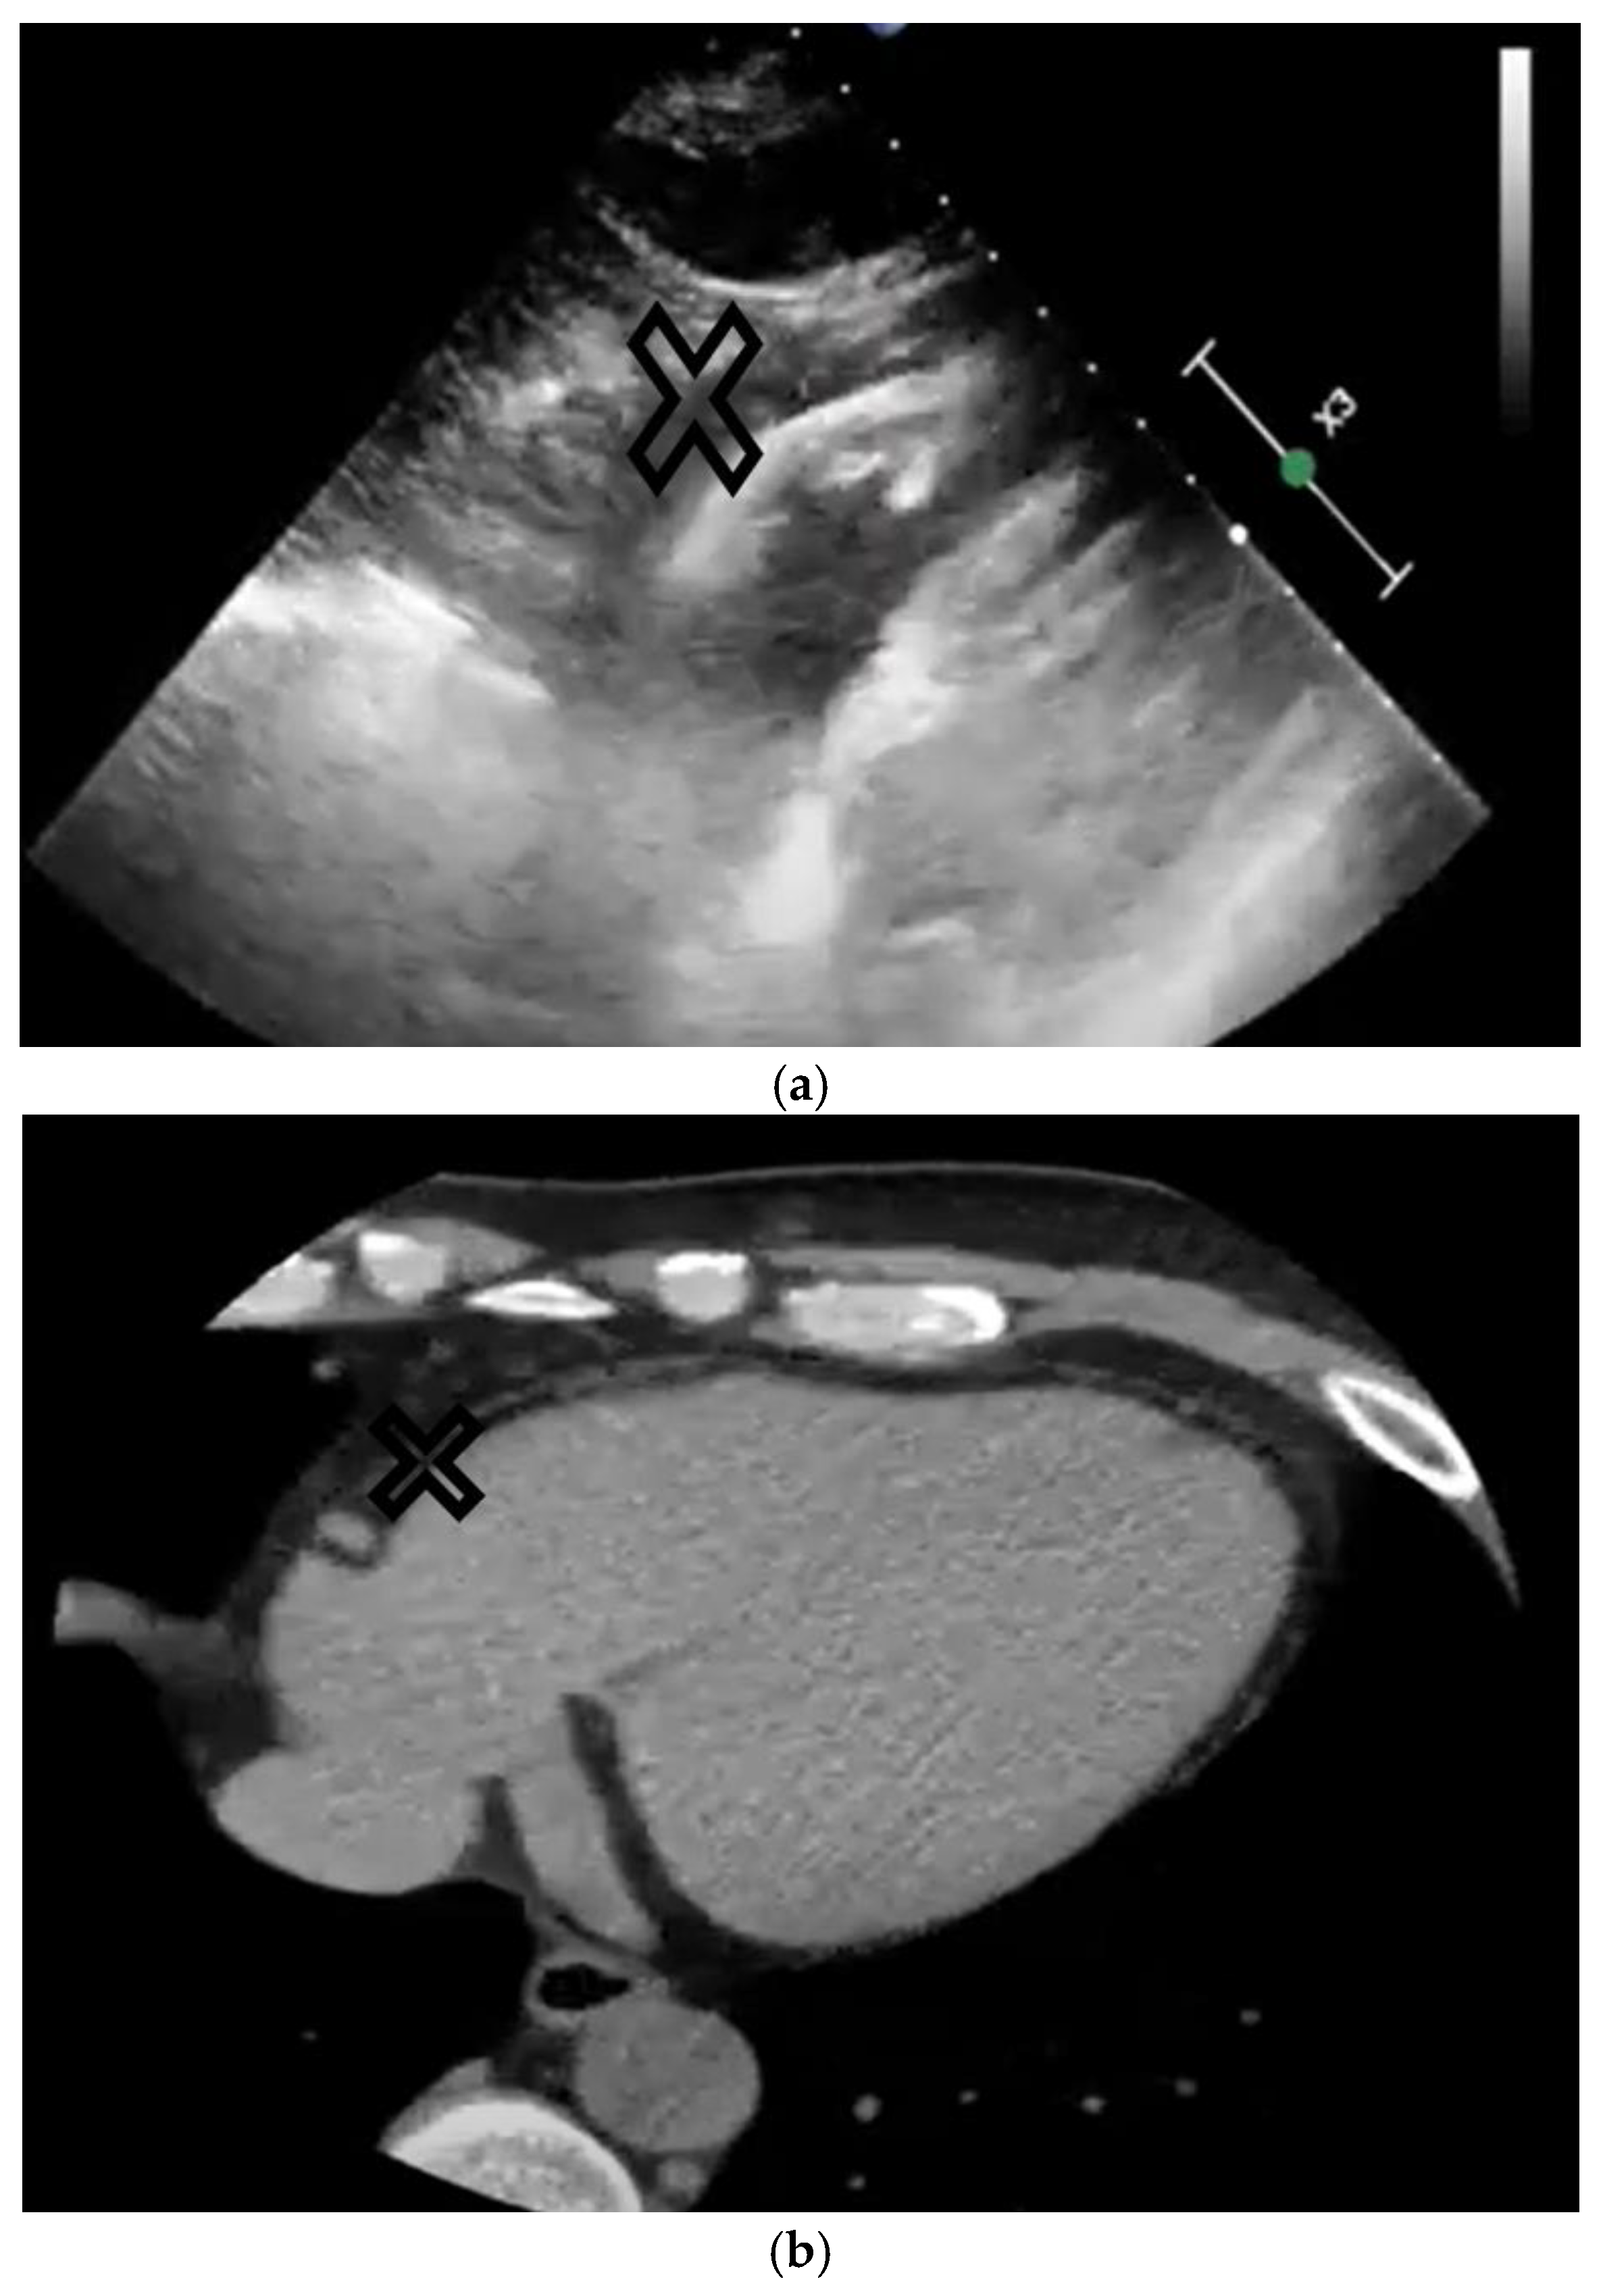

| Disease | Echocardiography | Cardiac CT | Cardiac MRI |

|---|---|---|---|

| ARVC | MAI is related to right ventricular (RV) dysfunction and the ventricular tachycardia substrate (conduction and repolarization disturbances) [38,39,40]. | MAI is related to the severity of the right ventricular structural disease, impaired RV function, and impaired LV systolic function. LV fat infiltration is a predictor of ventricular arrhythmias such as VT or VF, and sudden cardiac death, and allows a reclassification of 5-year risk of events [41,42,43,44,45]. | |